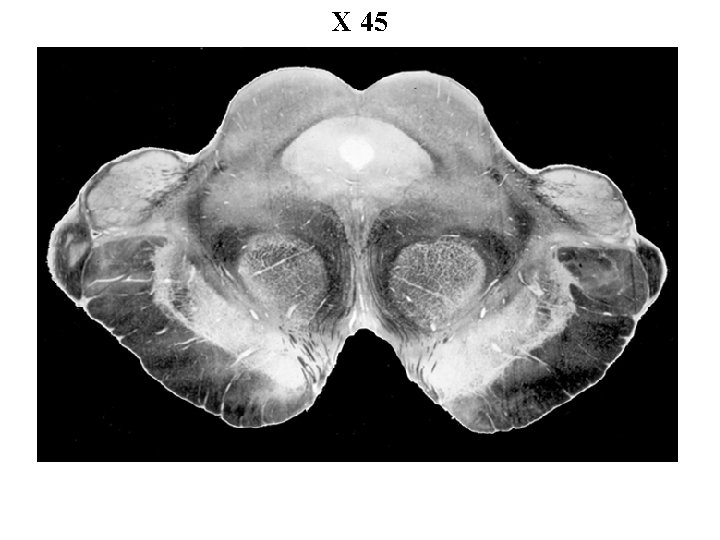

X 45